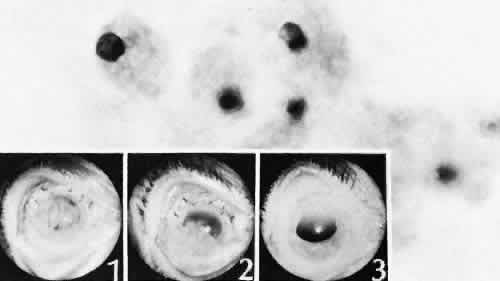

Elschnig's pearls (Fig. 41) result from aberrant attempts by lens cells attached to the lens capsule to form new lens “fibers.” Histologically, large, clear lens cells (“bladder cells”) are present behind the iris, in the pupillary space, or in both areas.

Fig. 41. Two cases of Soemmerring's ring cataract (retained lens cortex and capsule). A. Extensive opaque, well-delineated material is present in a ring-shaped configuration following a partially successful cataract extraction. The opacity is delimited by the remaining lens capsule and is located primarily in the region of the lens equator. B. The eye was examined at autopsy. The reaction is limited to the posterior chamber and within the lens capsule. Surrounding lens zonules and ciliary epithelium are not affected. C. Lens cortical material is retained in the equatorial area of the lens. This area is the least surgically accessible during cataract extraction and contains the tissue most likely to be left behind. This area also contains the cells with the greatest ability to react to trauma by undergoing fibrous metaplasia. The process is identical to anterior subcapsular cataract formation stimulated by anterior chamber inflammation. (Hematoxylin-eosin stain; × 6.) D. Residual lens cortical material ® can be clearly identified entrapped by residual lens capsule. The reaction in the lens may change the adhesive nature of the remaining anterior lens capsule. Posterior anterior synechia may form in these areas. (Hematoxylin-eosin stain; × 16.) E. In another case of retained lens material, the tissue change is less extensive and more translucent, resulting in pearl-like structures (Elschnig's pearls). The process producing this change is the same as the one in Soemmerring's ring formation, but the reaction is less extensive. Pearls are formed by aberrant attempts by lens cells to form new lens fibers. (Hematoxylin-eosin stain; × 69.)

Soemmerring's ring cataract results from the loss of anterior and posterior cortex and nucleus but with retention of equatorial cortex. Apposition of the central portions of the anterior and posterior lens capsule causes a doughnut configuration. Frequently, the doughnut is not complete, so that C- or J-shaped configurations result. Histologically, two balls of trapped and proliferated lens cells are encapsulated behind the iris leaf and connected by adherent anterior and posterior lens capsule in the form of a dumbbell.118